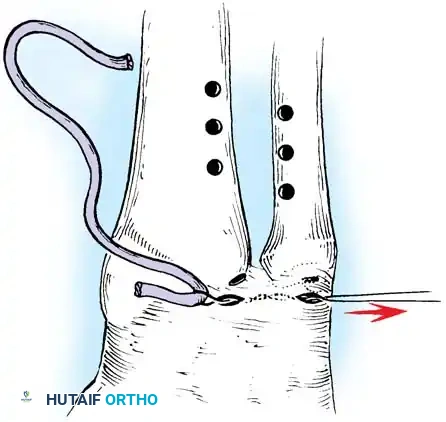

Preparation of the distal ulna: Drill holes are created at the fovea to facilitate transosseous suture passage for anatomic TFCC reattachment.

Transosseous Repair Technique:

1. Identify the foveal detachment arthroscopically or via an open dorsal ulnar approach.

2. Prepare the ulnar fovea down to bleeding bone using a burr or curette to stimulate a healing response.

3. Utilize a targeting guide to drill two converging osseous tunnels from the ulnar neck into the fovea.

Passing non-absorbable sutures through the osseous tunnels in the ulna to capture the peripheral edge of the TFCC.

- Pass strong, non-absorbable sutures (e.g., 2-0 FiberWire) through the TFCC using an outside-in or inside-out technique, then shuttle the suture limbs down the osseous tunnels.

The sutures are tied securely over the cortical bone bridge of the ulnar neck, restoring tension to the radioulnar ligaments.

- Tie the sutures over the ulnar cortical bridge with the forearm in neutral rotation to restore anatomic tension.